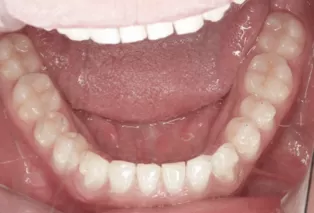

Intraoral photos